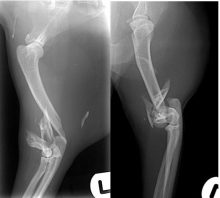

Treatment of a radius and ulna fracture in a Whippet

By Eastcott Referrals Orthopaedic Surgeon Fabio Frazzica A 1-year-old female Whippet presented with a distal diaphyseal, simple, transverse, closed ...